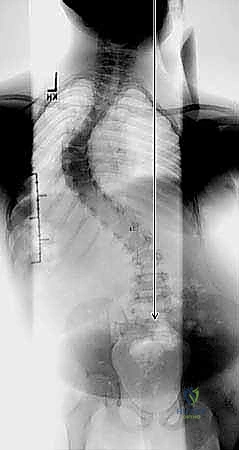

- الأشعة السينية الكاملة للعمود الفقري (Full Spine X-Rays):

- صور أمامية خلفية (AP) وجانبية (Lateral) والمريض واقف.

- يتم من خلالها قياس زاوية كوب (Cobb Angle)، وهي المعيار الذهبي لتحديد شدة الانحناء.

- أشعة الانحناء الجانبي (Side-Bending Films) وأشعة الشد (Traction Films):

- هذه الصور حاسمة جداً. يُطلب من المريض الانحناء لأقصى درجة يميناً ويساراً أثناء التصوير.

- الهدف هو تقييم "مرونة" الانحناء (Flexibility). إذا لم يتعدل الانحناء كثيراً في هذه الصور، فهذا يعني أن الانحناء "صلب" (Rigid)، وهذا هو المؤشر الرئيسي للحاجة إلى جراحة التحرير الأمامي.